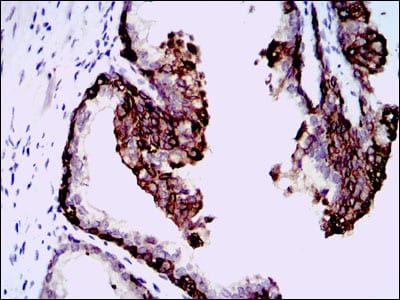

Immunohistochemical analysis of paraffin-embedded human cervical cancer tissues using NT5DC3 mouse mAb with DAB staining

Immunohistochemical analysis of paraffin-embedded human prostate tissues using NT5DC3 mouse mAb with DAB staining